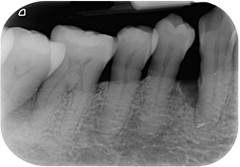

牙周病的檢查目的就是要了解患者牙周病的嚴重程度,以利訂定治療的計畫。檢查分兩項:第一項,測量牙周囊袋的深度,了解牙周病破壞的深度。第二項,拍攝全口X光片,了解牙齒周圍還剩多少骨頭,評估牙齒的預後。

探測牙周囊袋的深度

拍攝全口X光片